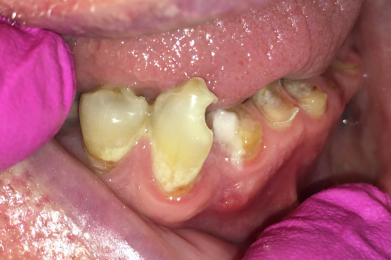

- Defekte oder braune, schwarze Stellen an den Zähnen, Kronen oder Brücken / Verweigerung von Essen wegen Heiß-/Kaltempfindlichkeit oder Empfindlichkeit süß-sauer / „Fährt rein!“

- Scharfe Kanten an den Zähnen / Verletzungen an Zunge oder Schleimhäuten fallen auf oder werden beklagt / Ständiges Spielen der Zunge an den Zähnen

- Feste, harte Kost wird verweigert / Gesicht bei fester Nahrung häufiger schmerzverzerrt

- Zahnbürste fehlt, Borsten sind weit gefächert und abgenutzt!